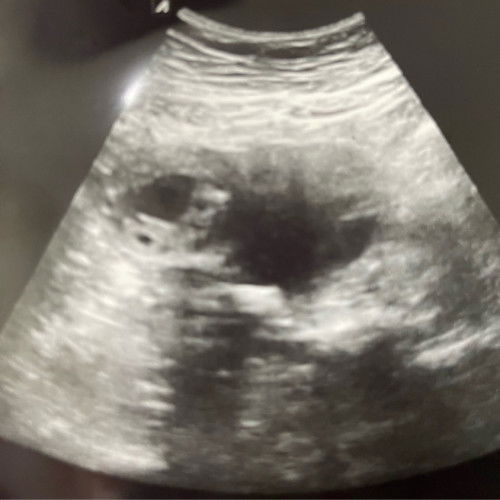

Doakan saya.6weeks.doc klinik swasta bgitau kantung tak berada di tempat sepatutnya (maybe ectopic) ada tak pengalaman yg sama pegi hosp then ada miracle#Needadvice #firsttimemom

Ectopic pregnancy